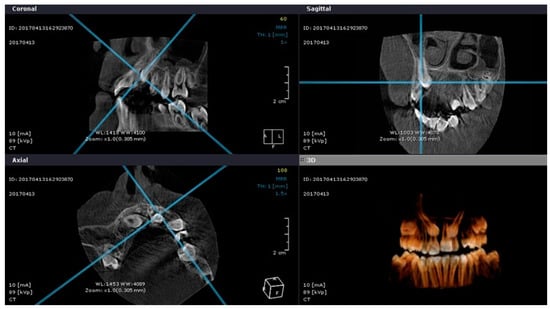

CBCT and Intra-Oral Scanner: The Advantages of 3D Technologies in Orthodontic Treatment

2. Materials and Methods